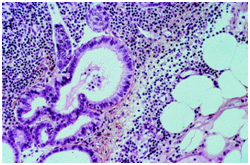

- Lymph node inclusions of mammary gland origin may be composed of deformed mammary gland ducts with divergent morphology and a dual cell population comprising of luminal cuboidal /columnar epithelial cells and basal cells depicting myopithelial differentiation (Figure 1).

- Mammary Inclusions: Axillary lymph nodes may frequently depict the ectopic mammary tissue. Inclusions of the breast tissue are demonstrated as mammary ducts in the subcapsular region. The cellular components described are the epithelium, myoepithelium and apocrine cells. Cystic spaces lined with low, uniform cuboidal epithelium lacking mitosis, hyperplasia or hyperchromasia may be evidenced.4 A singular layer of cuboidal epithelium interlining the tubules (hobnail appearance) or epithelial inclusions situated within or beneath the lymph node capsule may also be elucidated. A distinction is required from a metastatic breast carcinoma. The inclusions may delineate three categories i) glandular structures only ii) squamous cysts only iii) a combination of glandular and squamous epithelium.5

Figure 1 Origin of mammary inclusions

Figure 3 Benign mammary inclusions with glandular configuration.